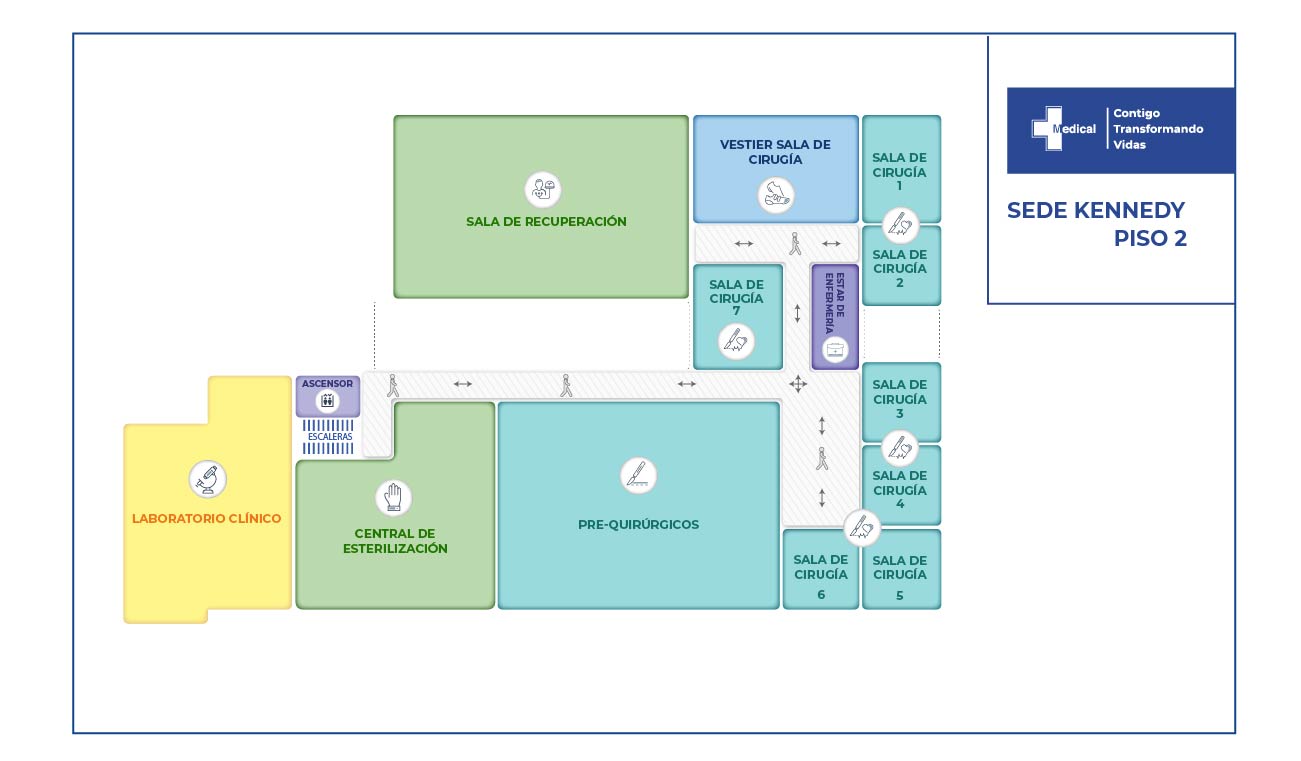

El paciente fue sometido a 3 cirugías y 6 procedimientos realizados entre cirugía general como tratamiento a través de toracostomia, de igual manera descarto lesiones abdominales por trauma cerrado y neurocirugía realiza la reparación de la fistula espinal de líquido cefalorraquídeo, la reducción abierta de fractura de columna vertebral y artrodesis de la región torácica (consistió en la colocación de 20 tornillos transpediculares, 2 barras verticales y 1 conector transverso, esto en 10 segmentos).